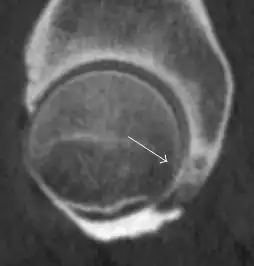

Intra-articular osseous causes of pain include several conditions: avascular necrosis (AVN), transient osteoporosis of the hip (TOH), tumors, and stress or insufficiency fractures. All these entities may present with a pattern of bone marrow edema characterized by decreased signal intensity on T1 weighted images and increased signal intensity on fluid sensitive sequences, such as fat saturated T2-weighted or STIR images. When there is no evidence of a focal lesion associated with the edema pattern, TOH is suspected. When a band of low intensity is seen inside the edematous area, the shape and length of this band become important. It is generally convex to the articular surface in the case of subchondral stress or insufficiency fractures, whereas it is concave, circumscribing all of the necrotic segment, in cases of AVN. When doubts do persist, gadolinium-enhanced MRI tends to show that the proximal portion beyond the band is enhanced in fractures but is not in AVN.[1]

MRI has been shown to have 100% sensitivity and specificity in prospective studies of occult hip fractures. These fractures were diagnosed by bone marrow edema and a low signal fracture line, mainly on T1 or T2 weighted images (Figure 10).[1]

Figure 10: